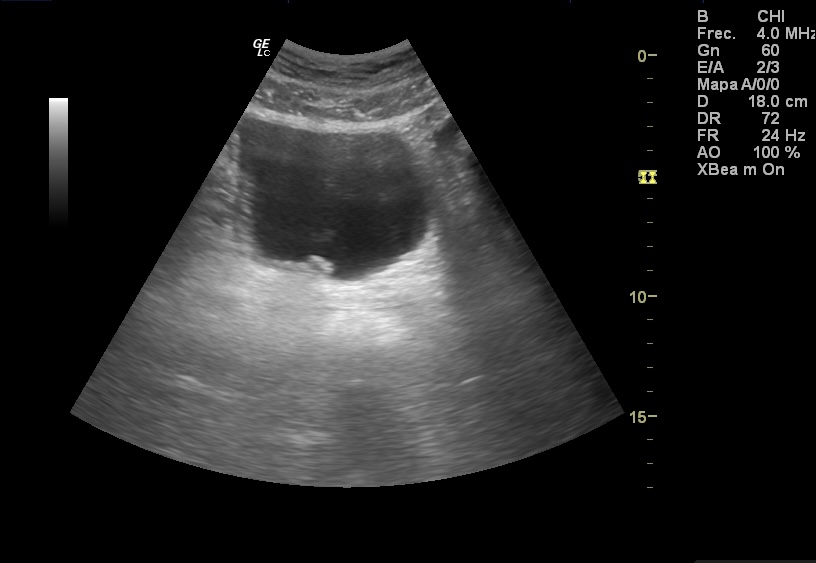

Hallazgos ecográficos

Ecografía abdominal y renal sin hallazgos. En la vejiga se aprecia una lesión polipoidea hiperecogénica irregular de bordes lobulados, de 1,23 cm de diámetro dependiente de la pared vesical en la región del trígono vesical.